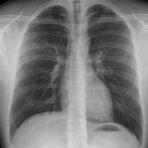

Röntgen Lunge

Röntgenaufnahme des Thorax

• Entzündungsdiagnostik (Pneumonie, gehäufte Bronchitis)

• Pleuraerguss

• Tumorverdacht

• Lungenemphysem

• Herzinsuffizienz

• Therapiekontrolle